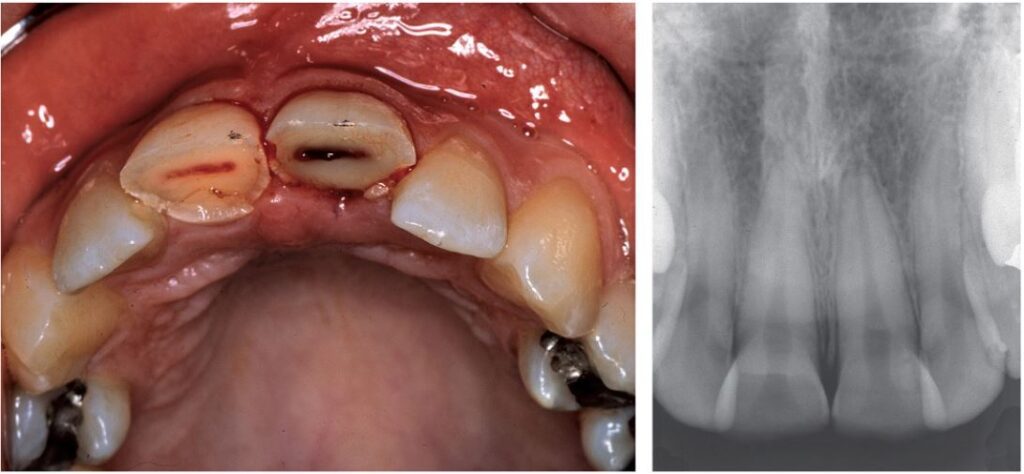

Gãy thân răng phức tạp thường xuất hiện xuất huyết nhẹ ở phần tủy lộ ra (Hình 13.5).

Sự tăng sinh của mô tủy (tức là polyp tủy) có thể xảy ra khi việc điều trị ở răng chưa đóng chóp bị trì hoãn nhiều ngày (Hình 13.6).

Việc kiểm tra bằng X quang bổ sung thông tin quan trọng vào đánh giá lâm sàng có thể ảnh hưởng đến việc điều trị trong tương lai, chẳng hạn như kích thước tủy và giai đoạn phát triển chân răng.

Hơn nữa, X quang còn có tác dụng như một bản ghi để so sánh ở những lần tái khám sau, đặc biệt là để xác minh hàng rào mô cứng trên tủy bị lộ khi không thể xác minh lâm sàng. Tuy nhiên, cần lưu ý X quang chỉ có thể ước tính kích thước tủy.

Thực tế xoang tủy thường lớn hơn và khoảng cách từ sừng tủy đến rìa cắn thường nhỏ hơn khoảng cách quan sát thấy trên X quang. Trong một số ít trường hợp, sự dịch chuyển của răng sữa có thể dẫn đến gãy mầm răng vĩnh viễn, dấu hiệu này có thể được thể hiện trên phim X quang.